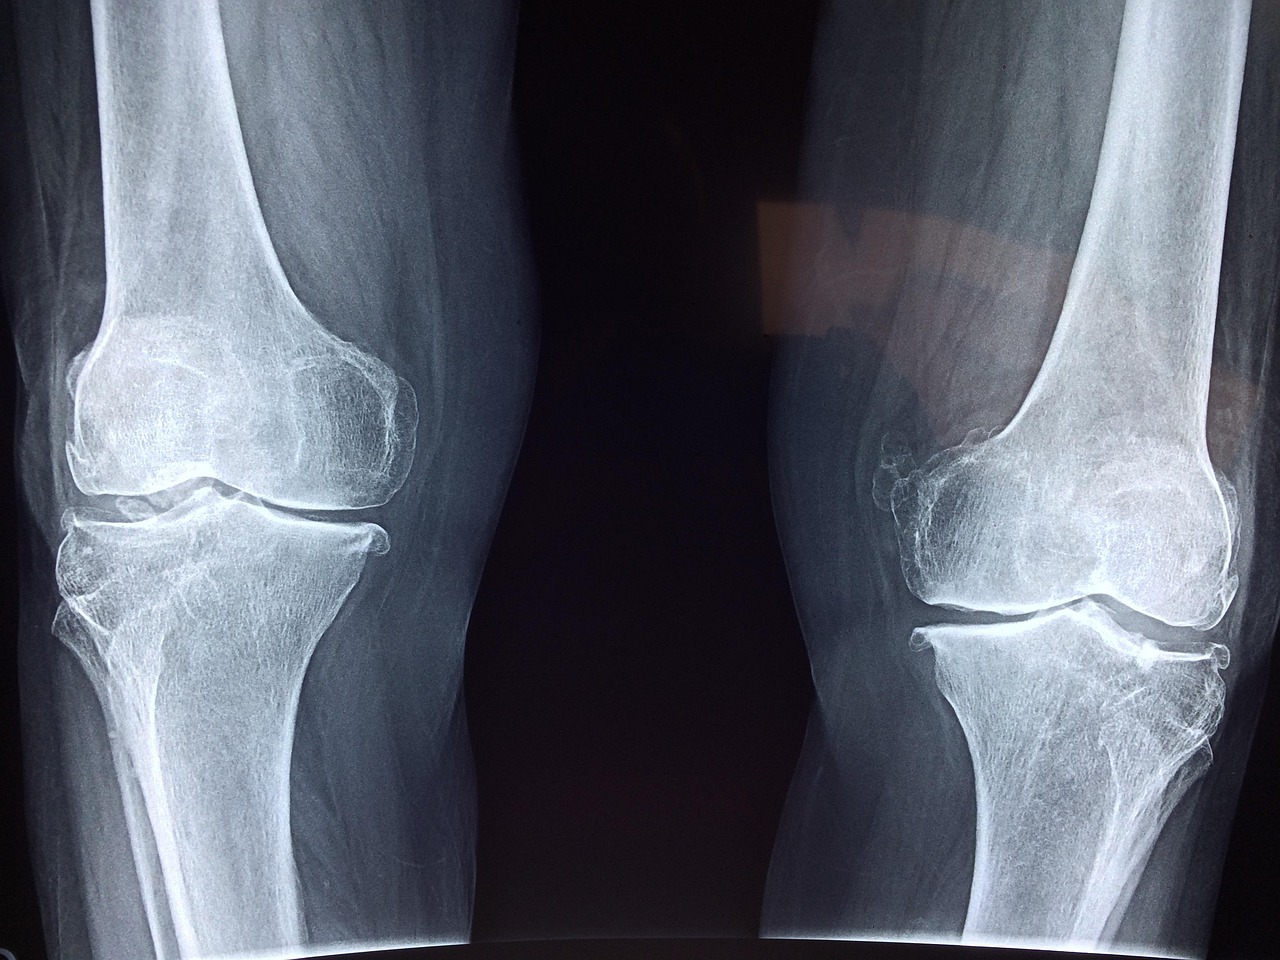

무릎 인공관절 수술 후 빠른 회복을 위한 5가지 팁

무릎 인공관절 수술은 무릎 관절의 통증과 기능 저하로 고생하는 많은 환자들에게 희망이 되고 있습니다. 최신 의료 기술과 전문 의료진이 함께하는 무릎인공관절병원에서는 안전하고 효과적인 치료를 제공하고 있는데요. 수술 전후 관리부터 회복까지 체계적인 서비스를 경험할 수 있습니다. 오늘은 무릎 인공관절병원에 대해 자세히 살펴보도록 하겠습니다. 궁금한 점들을 모두 알려드릴게요! 자주 묻는 질문 (FAQ) 📖 Q: 무릎 인공관절 수술은 … Read more